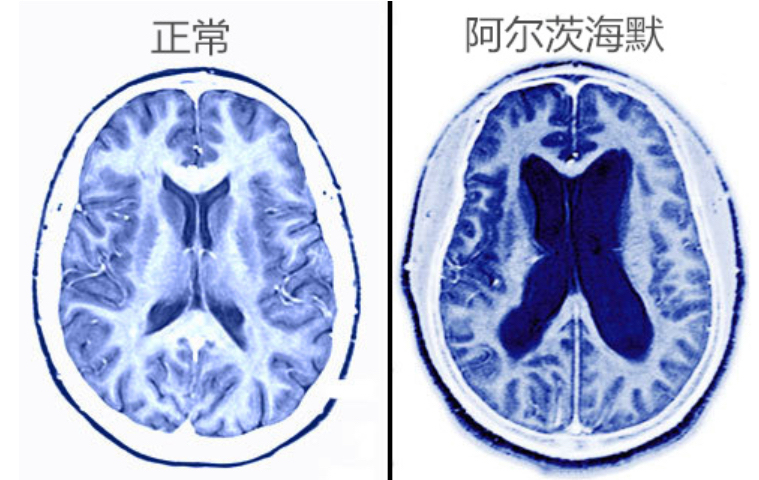

ADDS-100认知功能障碍筛查系统采用国际通用的MMSE和ADL等量表,进行语音及图像输出,并记录患者的反应,对检测结果进行快速统计,提供即时诊断数据,对认知功能障碍进行筛查,医师结合动态脑电图(EEG)监测结果,通过对不同时频空域及交互干预下,α波、β波和θ波的奇异值分解矩阵参数和复杂度、近似熵、小波熵等非线性特征量的提取,应用变尺度最大相关最小冗余算法,实现变尺度特征选择,为临床提供认知功能障碍及AD早期证据。